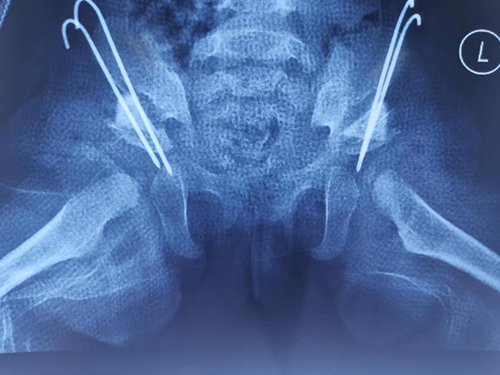

诊断明确后,王恒冰团队术前反复讨论,仔细研究患儿的各项情况,为孩子制定了最佳的治疗方案,术后涵涵小朋友恢复良好。